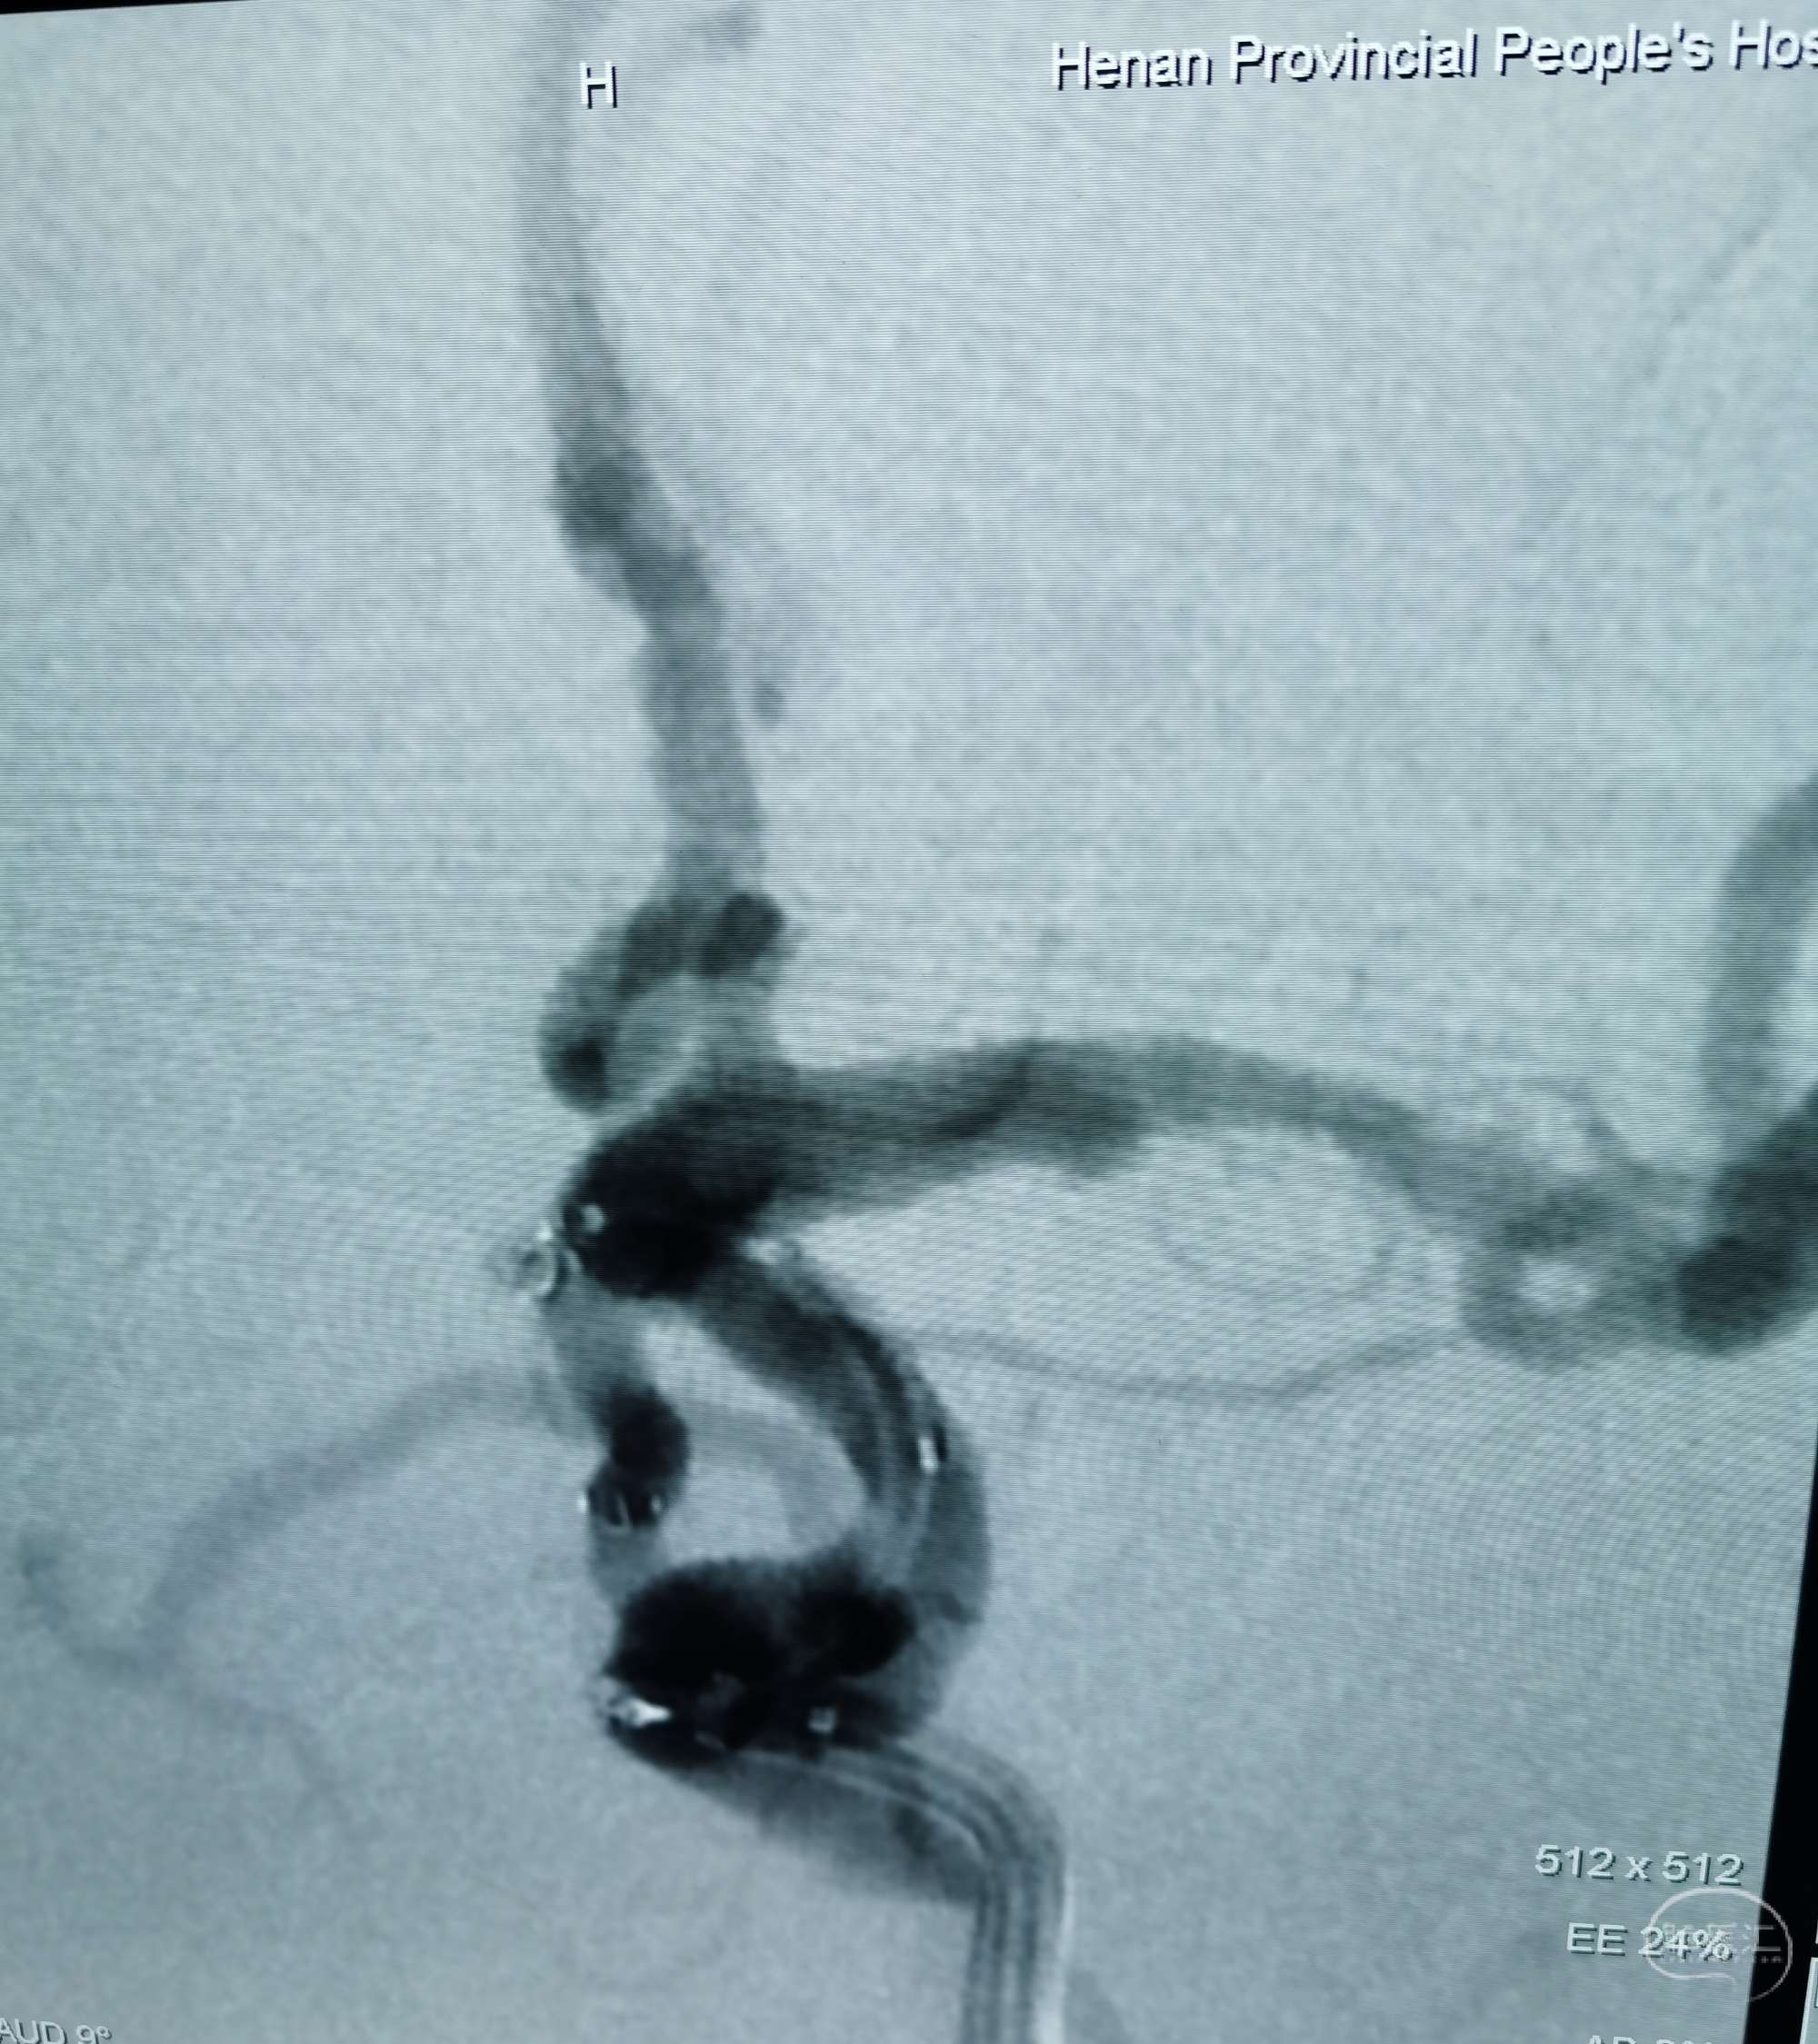

DSA示左侧后交通微小动脉瘤,起自后交通,血泡样。

3D示动脉瘤大小约1.36✘1.40mm

胚胎型后交通动脉。

压颈DSA造影示左侧P1缺如。

支架Atlas4.0×21mm辅助栓塞动脉瘤,支架放置后交通动脉。

target1.0×3.0,1.0×2.0mm两枚coiling.

动脉瘤栓塞良好。

后交通及载瘤动脉通畅。